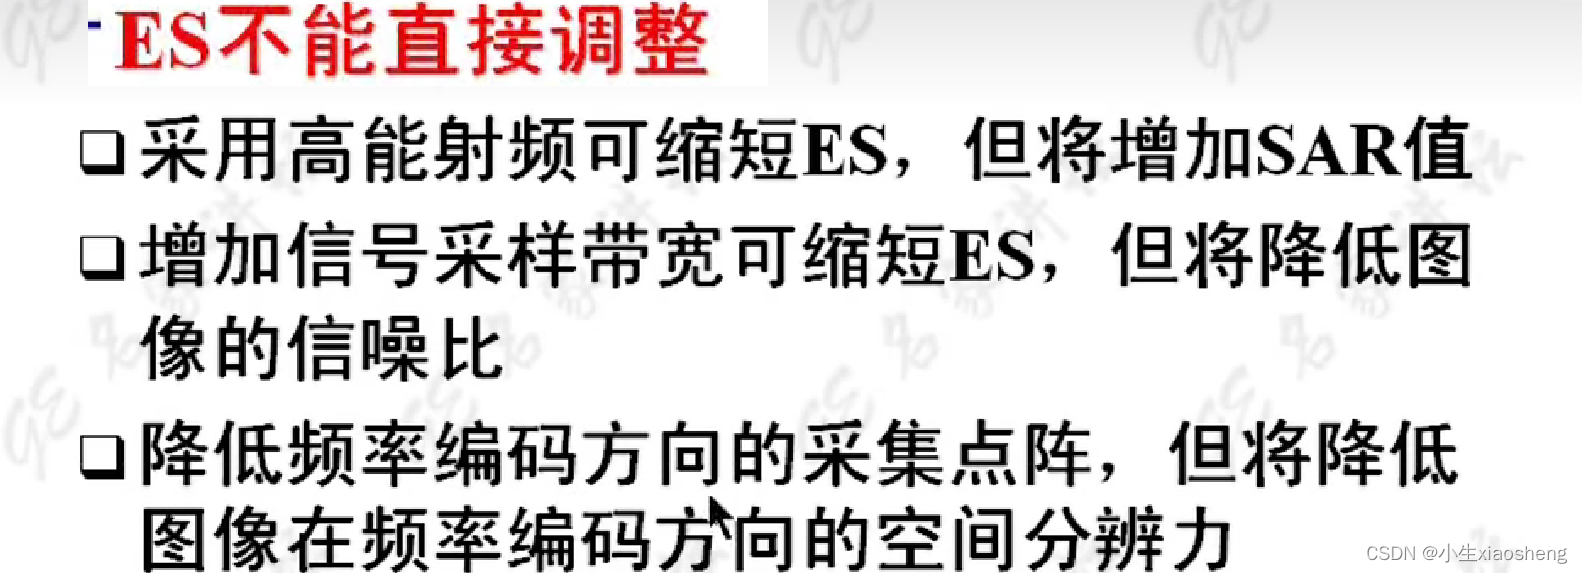

因为这里有很多的180度,所以一次能填充很多K空间线。两个90度之间的时间还是叫做TR,180度的个数叫做ETL,90度到中间个数的180度叫做有效TE,两个180度之间的叫做ES。